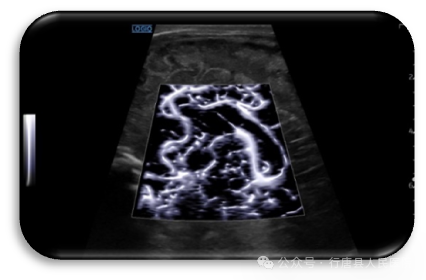

从多个维度观察血管、组织的血流灌注,明确诊断,提高诊断信心。

Radiant flow立体血流成像 利用血流的动力学信息,如流速、信号强度、方差定义为不同颜色及高程,以3D效果呈现血流,以提高空间分辨力、动力学信息显示及细微血流显示连续性,支持所有成像探头及血流模式。